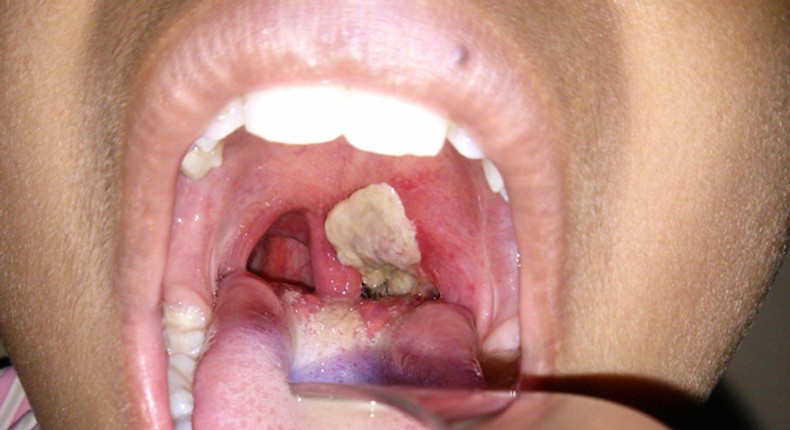

Speaking on the rising cases of the disease at a press conference on Monday, the Director-General of the Nigeria Centre for Disease Control and Prevention (NCDC) Dr. Ifedayo Adetifa said that out of the 8,406 cases in Nigeria, 73.7 % of the victims were between one year and 14 years.

“Of the 8,406 confirmed cases, 6,202 (73.7 %) were aged one to 14 years. Infants: less than 1%; one to four years: 14.40%; five to nine years: 32.2%; 10 to 14 years: 27.1%; adults above 20 years: 15%